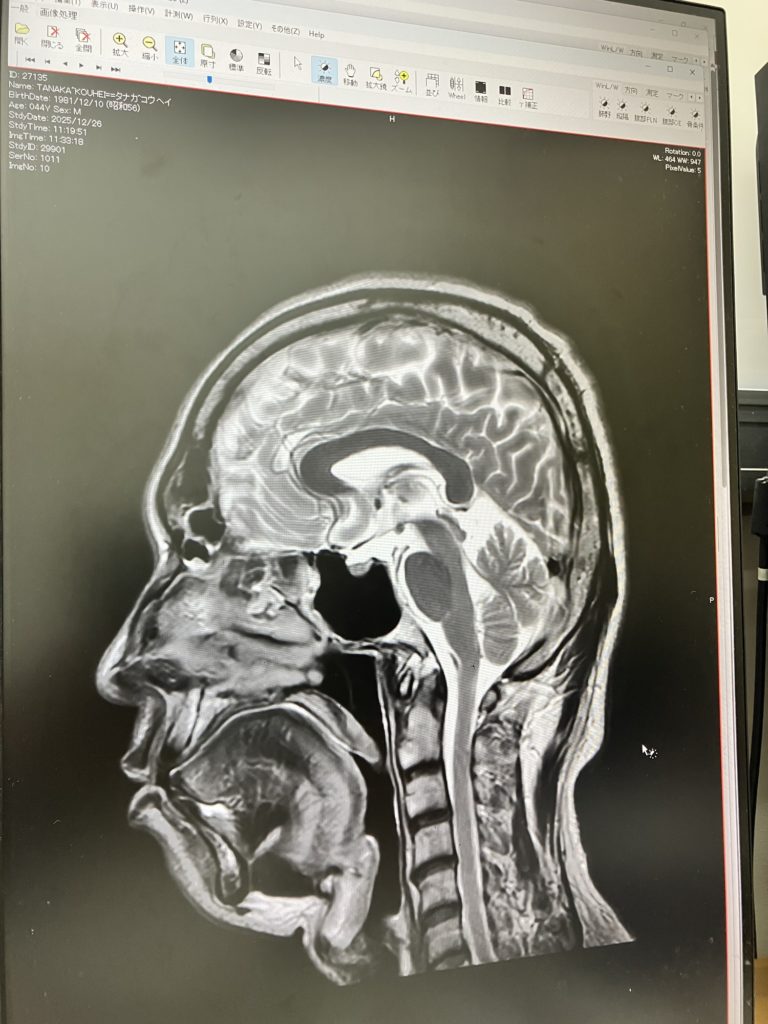

くも膜下に出血?なにか腫瘍があって痛いのかな?→MRIで輪切りして診てもらう。

今年、8年振りにMRI撮りました。

撮影前に先生は「撮るのは否定の意味が強いかなぁ。他の病気が無いかどうかっていうね。」

何もありませんでした。

なので群発頭痛です。ただの。安定の。群発頭痛。他に当てはまらんし。みたいな。